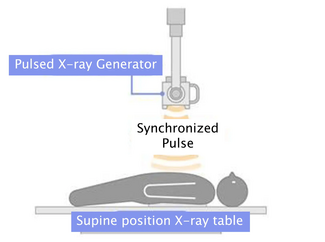

Case Report. A 66-year-old male smoker with long-standing systemic arterial hypertension was seen at our facility, complaining of a 5-month crescendo angina and a syncopal episode during an angina event. The ECG showed a first-degree AV block and a possible septal infarct. At the time of presentation he was asymptomatic, a TL-201 gated myocardial perfusion imaging study showed a nontransmural myocardial infarction of the apex with anteroseptal and lateral wall extension with severe residual ischemia as well as mild inferolateral ischemia and moderate left ventricular dysfunction.

The patient was sent for coronary artery catheterization that was performed via right radial artery approach (6 Fr Glidesheat and 5 Fr Optitorque radial TIG catheter Terumo interventional systems). The angiographic findings were a mild mid left main coronary artery (LMCA) lesion, a partially recanalized chronic left anterior descending (LAD) coronary artery proximal occlusion with excellent collaterals, severe proximal left circumflex (LCX), mid obtuse marginal (OM) stenosis (Figure 1A), and a severe stenosis of the bifurcation compromising the posterior descending and posterolateral branches of the right coronary artery (not shown in figures).

The patient was sent for coronary artery catheterization that was performed via right radial artery approach (6 Fr Glidesheat and 5 Fr Optitorque radial TIG catheter Terumo interventional systems). The angiographic findings were a mild mid left main coronary artery (LMCA) lesion, a partially recanalized chronic left anterior descending (LAD) coronary artery proximal occlusion with excellent collaterals, severe proximal left circumflex (LCX), mid obtuse marginal (OM) stenosis (Figure 1A), and a severe stenosis of the bifurcation compromising the posterior descending and posterolateral branches of the right coronary artery (not shown in figures).